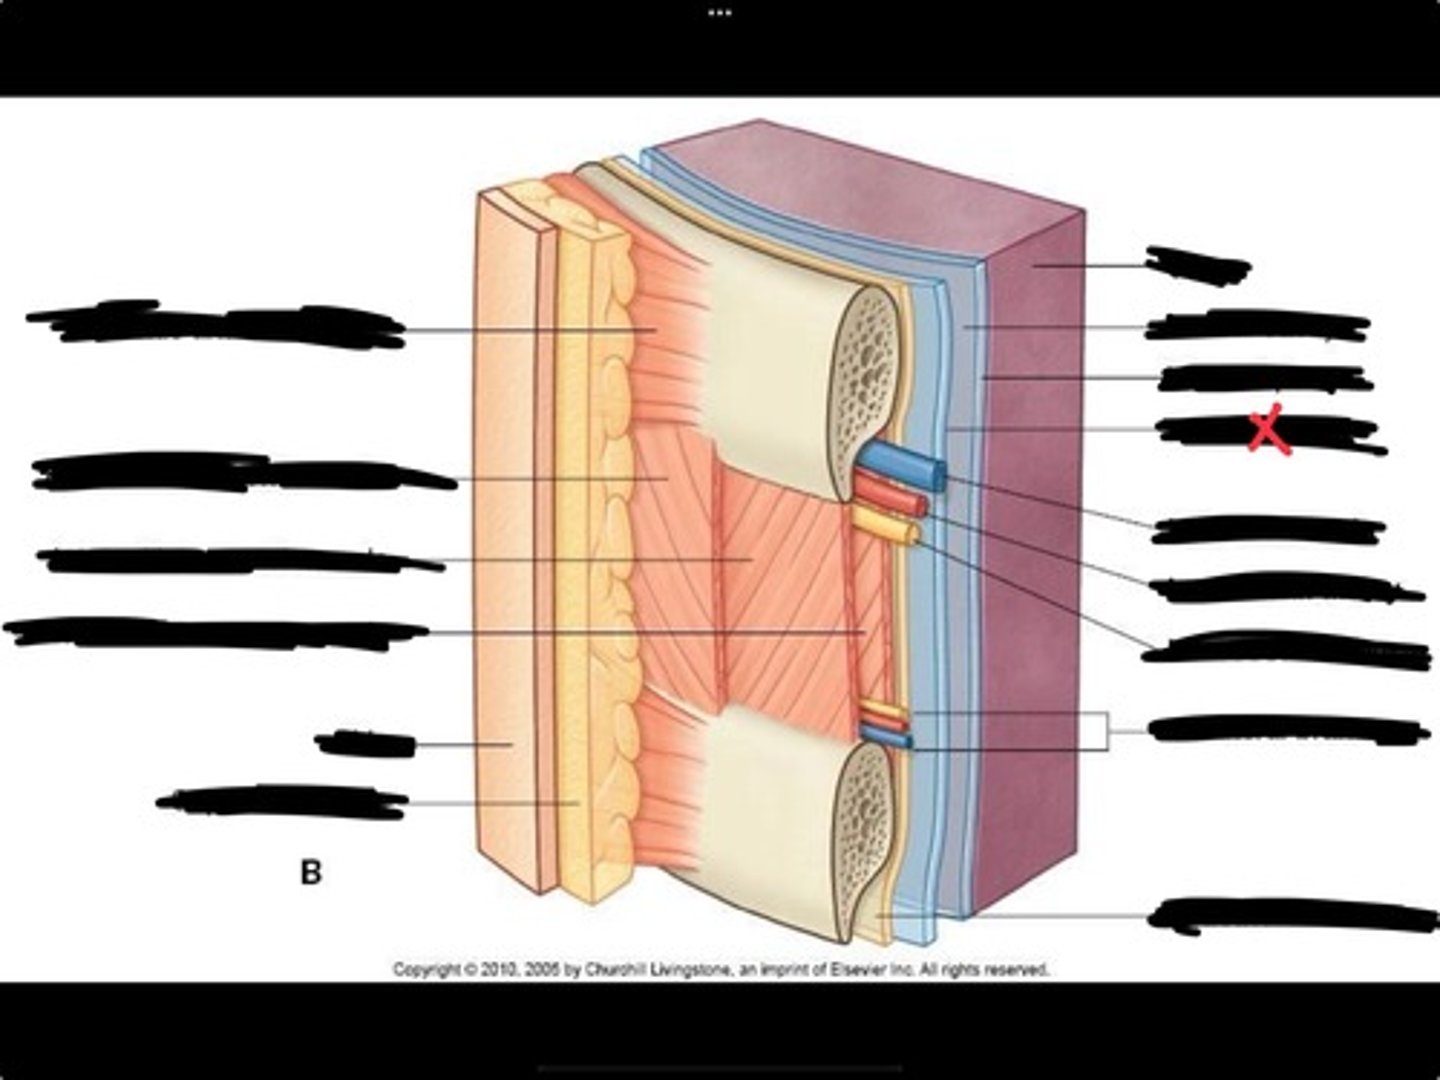

Innermost intercostal muscle

Skin

Internal intercostal muscle

External intercostal muscle

Serratus anterior muscle

Lung

Pleural cavity

Visceral pleura

Parietal cavity

Intercostal vein

Intercostal artery

Collateral branches

Intercostal nerve

Endothoracic fascia